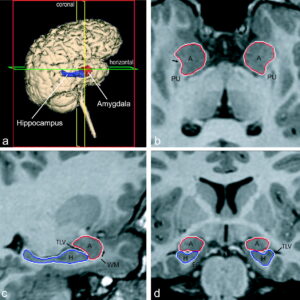

L'amigdala, oltre ad essere il centro delle emozioni e delle intuizioni, scandisce, quantifica e gestisce ogni nostro atto di generosità....